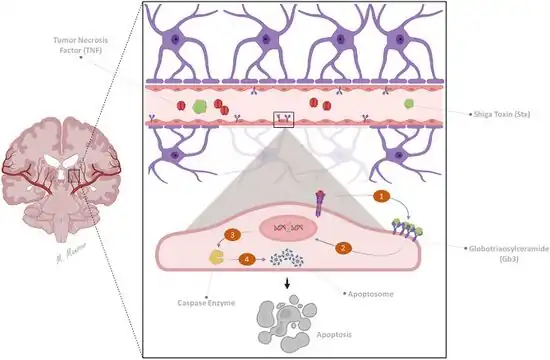

HUS is one of the thrombotic microangiopathies, a category of disorders that includes STEC-HUS, aHUS, and thrombotic thrombocytopenic purpura (TTP). STEC-HUS occurs after ingestion of a strain of bacteria expressing Shiga toxin(s), usually types of E. coli, that expresses verotoxin (also called Shiga-like toxin). E. coli can produce stx1 and/or stx2 Shiga toxins, the latter being more dangerous. A combination of both toxins in certain ratios is usually associated with HUS. These Shiga toxins bind GB3 receptors, globotriaosylceramide, which are present in renal tissue more than any other tissue and are also found in central nervous system neurons and other tissue. Children have more GB3 receptors than adults which may be why children are more susceptible to HUS. Cattle, swine, deer, and other mammals do not have GB3 receptors, but can be asymptomatic carriers of Shiga toxin-producing bacteria. Some humans can also be asymptomatic carriers. Once the bacteria colonizes, diarrhea followed by bloody diarrhea, hemorrhagic colitis, typically follows. STEC-HUS is usually preceded by a prodrome of diarrhea, which is often bloody, and is caused by Shiga-like toxin-producing bacteria such as enterohemorrhagic Escherichia coli (EHEC), of which E. coli O157:H7 is the most common serotype.[26] Other serotypes also cause disease and can emerge as new causes of STEC-HUS, as occurred with E. coli O104:H4, which triggered a 2011 epidemic of STEC-HUS in Germany.[34]

The typical pathophysiology of HUS involves the binding of Shiga-toxin to the globotriaosylceramide (Gb3; also called ceramide trihexoside which accumulates in Fabry disease) receptor on the surface of the glomerular endothelium.[35] This action includes a cascade of signaling events leading to apoptosis and binding of leukocytes to endothelial cells. The Shiga-toxin-activated endothelial cells then become thrombogenic (clot-producing) by a mechanism that is not fully understood,[36] though they have been shown to induce the release of cytokines and chemokines that are implicated in platelet activation.[37] Additionally, the binding action of Shiga-toxin inactivates a metalloproteinase called ADAMTS13, the deficiency of which causes the closely related TTP. Once ADAMTS13 is disabled, multimers of von Willebrand Factor (vWF) form and initiate platelet activation, causing microthrombus formation. The activation of platelets resulting from inhibition of ADAMTS13 is due to the hyperactivity of large multimers of uncleaved vWF. The arterioles and capillaries of the body become obstructed by the resulting complexes of activated platelets, which have adhered to the endothelium via large multimeric vWF. Through a mechanism known as microangiopathic hemolysis, the growing thrombi lodged in smaller vessels destroy red blood cells (RBCs) as they squeeze through the narrowed blood vessels, forming schistocytes, or fragments of sheared RBCs.[27] The presence of schistocytes is a key finding that helps to diagnose HUS. Typically, this hemolysis results in a hemoglobin level of less than 80 g/L.

Shiga-toxin directly activates the alternative complement pathway and also interferes with complement regulation by binding to complement factor H, an inhibitor of the complement cascade. Shiga-toxin causes complement-mediated platelet, leukocyte, and endothelial cell activation, resulting in systemic hemolysis, inflammation and thrombosis.[38][39][40] Severe clinical complications of TMA have been reported in patients from 2 weeks to more than 44 days after presentation with STEC-HUS, with improvements in clinical condition extending beyond this time frame, suggesting that complement activation persists beyond the acute clinical presentation and for at least 4 months.[41]